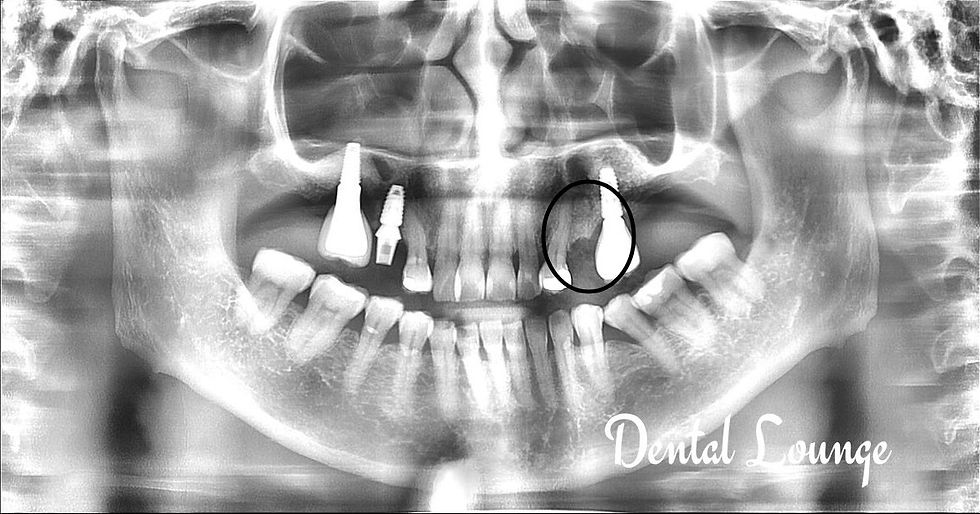

Surgical Removal of Deep Horizontally Impacted Lower Right Wisdom Tooth (#48) with Extraction of Upper Right Wisdom Tooth (#18)

Surgical removal of a deep horizontally impacted lower wisdom tooth (#48) with CBCT guidance to ensure safe extraction and protection of surrounding nerves and sinus structures.